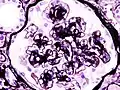

Гистопатологическая картина диабетического гломерулосклероза с нефротическим синдромом. Другой почечный клубочек.